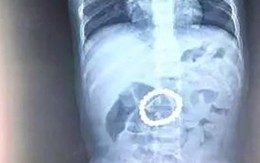

Hình ảnh chụp X-quang dạ dày của bé trai 14 tháng tuổi và lời cảnh tỉnh các bố mẹ về món đồ chơi mà trẻ nhỏ rất thích

Sống khỏe 2018-05-27T11:36:00Sau khi con trai liên tục sốt và nôn trớ, bố mẹ cậu bé đã nhanh chóng đưa con đến bệnh viện khám và kết quả chụp X-quang thật bất ngờ: có một vật lạ hình vòng tròn nằm trong dạ dày bé.